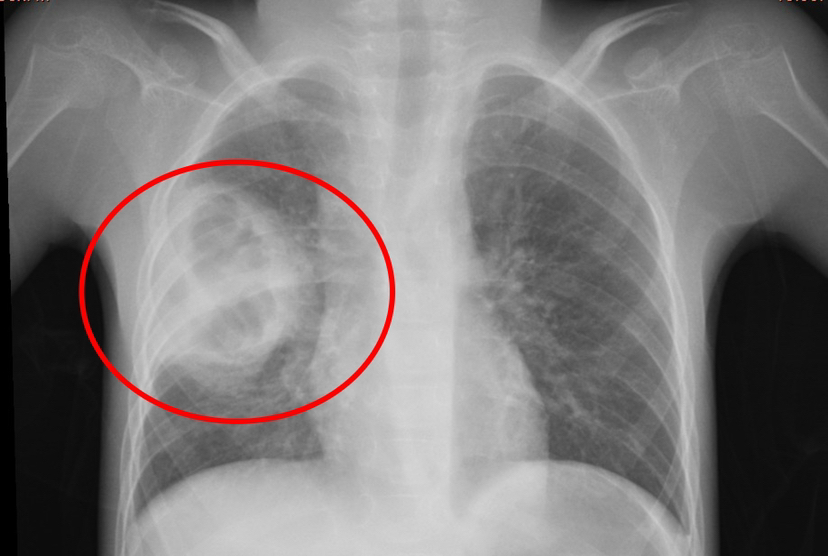

患兒小小,患有腦癱與藥物難治性癲癇,重度營養不良,7歲體重僅10公斤,因長期臥床導致肺部感染并發肺膿腫,入院時情況極為復雜,胸部CT顯示肺膿腫、肺炎合并胸腔積液,高熱不退、呼吸困難,驚厥頻發,治療難度極大,家屬幾近絕望,甚至動過放棄治療的念頭。